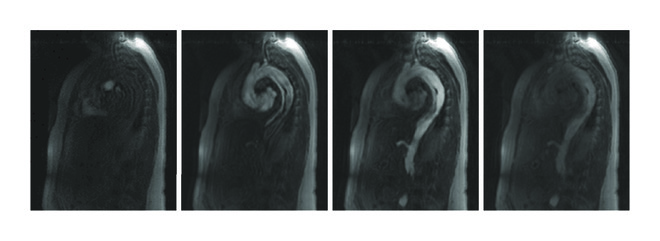

A 1.5 T clinical MR scanner (Magnetom Symphony, Siemens, Erlangen, Germany) and two standard phased array body coils were used for MRI acquisition. Patients were positioned in supine position. For TR-MRA, a time-resolved three-dimensional gradient echo pulse sequence with view sharing (time-resolved angiography with stochastic trajectories, TWIST) was applied in sagittal orientation (Figure 1). The following sequence parameters were used: field of view 500 × 325 mm; in-plane resolution, 2.6 × 2.6 mm; slice thickness, 3 mm; 30 slices per slab; parallel imaging GRAPPA, PAT factor 2; repetition/echo time (TR/TE), 1.82/0.68 ms; flip angle, 40°; acquisitions every 2.4 s over a period of 2 min. Acquisition was performed during shallow breathing. Gadolinium contrast agent (Gd-DTPA, Magnevist, Bayer Schering, Germany) was administered with a dose of 0.1 mmol/kg body weight via an 18 G cannula in an antecubital vein with an injection rate of 3 ml/s followed by a saline flush of 20 ml at the same injection rate using an automatic power injector.

MRI data was transferred to Syngo MultiModality Workplace VE36A (Siemens, Erlangen, Germany). All data was analyzed by one radiologist experienced in cardiovascular imaging. Regions of interest were placed in the lumen of the nondissected distal ascending aorta just proximal the aortic arch and of the true and false lumen of the descending aorta at the level of the diaphragm covering as much of the respective lumen as possible. From the resulting time-intensity-curves, the following parameters were computed as it has been described in literature (Figure 2) [18, 21]: time-to-peak (TTP) intensity, full width at half maximum (FWHM), and upward slope and downward slope. Furthermore, the difference between the time step with peak intensity in the false lumen and the time step with peak intensity in the nondissected proximal aorta was calculated.